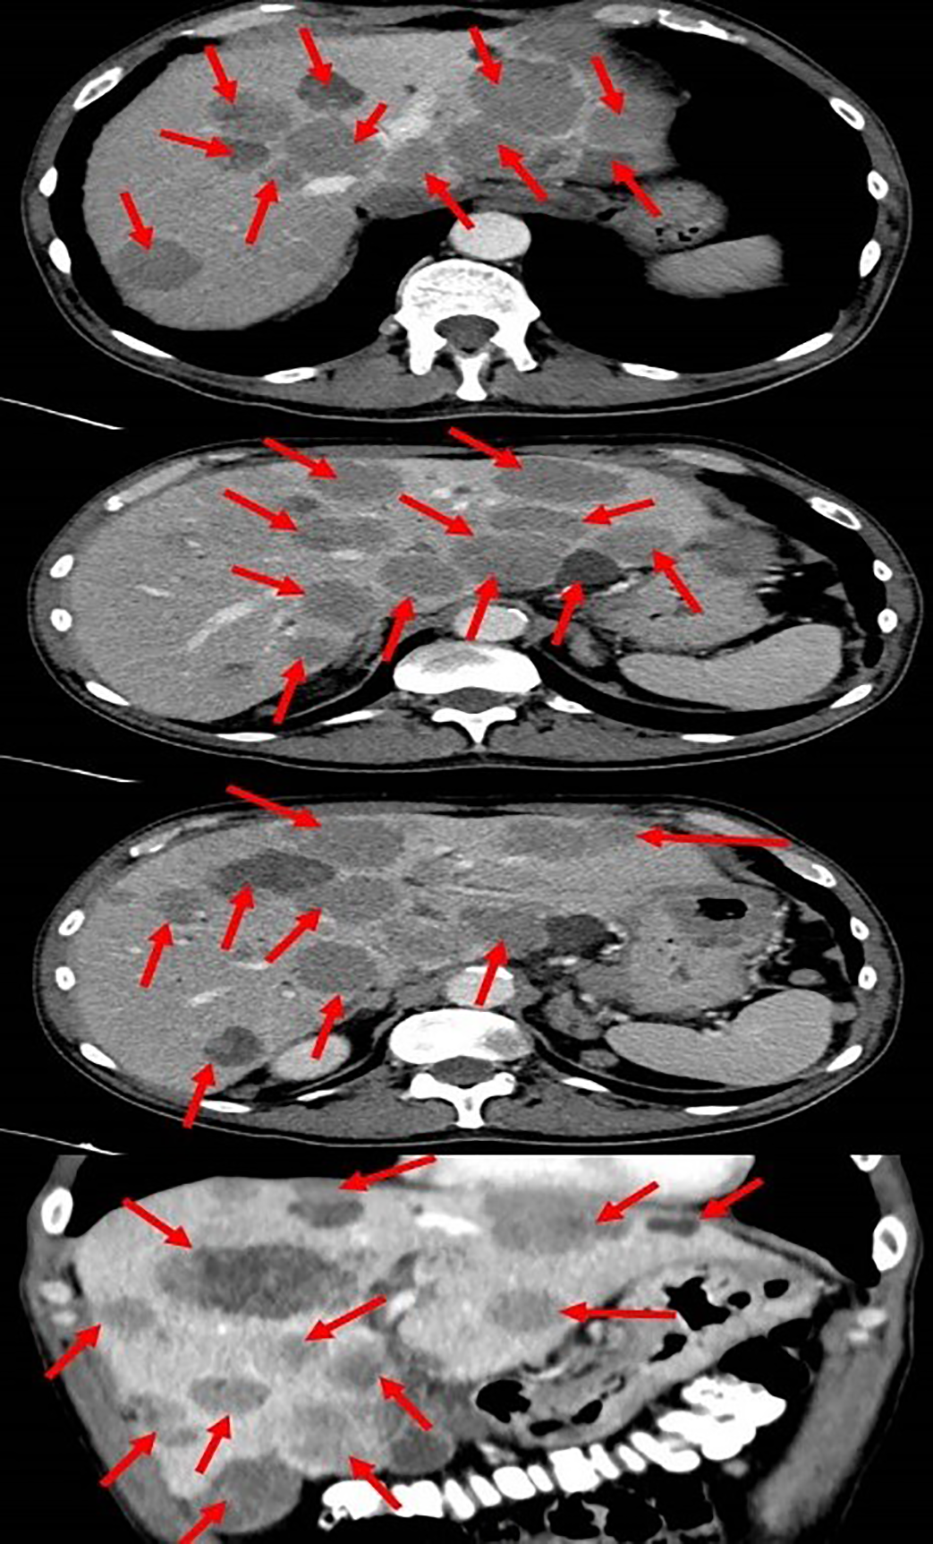

Initial blood tests revealed low hemoglobin levels of 7.1 gm/dL (normal range: 14-16 gm/dL), accompanied by mild leukocytosis and thrombocytosis. Blood chemistry showed an elevation in both total and direct bilirubin of 11.05 and 6.97 gm/dL respectively (nor-mal range: 0.3-1.2 gm/dL), and elevated liver enzymes, especially in alkaline phosphatase and gamma-glutamyl transferase (GGT). The lactate dehydrogenase (LDH) level was 1193 (IU/L). These results were consistent with obstructive jaundice, with the elevated levels of alkaline phosphatase and GGT suggesting intrahepatic cholestasis. Chest radiography showed small nodules in the left lung that were suspected of being metastatic processes. A total body computed tomography (CT) scan (Figure 1) revealed hepatomegaly (25*19 cm in diameter), several nodules in both lungs suspected of being metastasis (the biggest was 15 mm in diameter), enlargement of the lymph nodes in the hilum of both lungs, a space occupying lesion (SOL) in the vertebral area (D10), a SOL in the fundus of the stomach (6 cm in diameter), multiple SOLs in the liver (the biggest was 5 cm in diameter), enlargement of the lymph nodes in the hilum of the liver (the biggest 5 cm in diameter, SOLs in the head of the pancreas, SOLs in the bilateral adrenals, and several enlarged lymph nodes in the abdominal space.

Figure 1

Total body computed tomography scan showing the metastatic melanoma in the liver (red arrows).